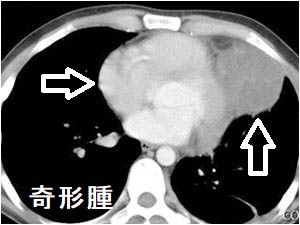

奇形腫

手塚治虫のブラックジャックで有名な奇形腫。内部に歯・皮脂などを含み、エコーで内部不均一に見えます。むしろCTの方が、内部の成分を明瞭に鑑別できます。